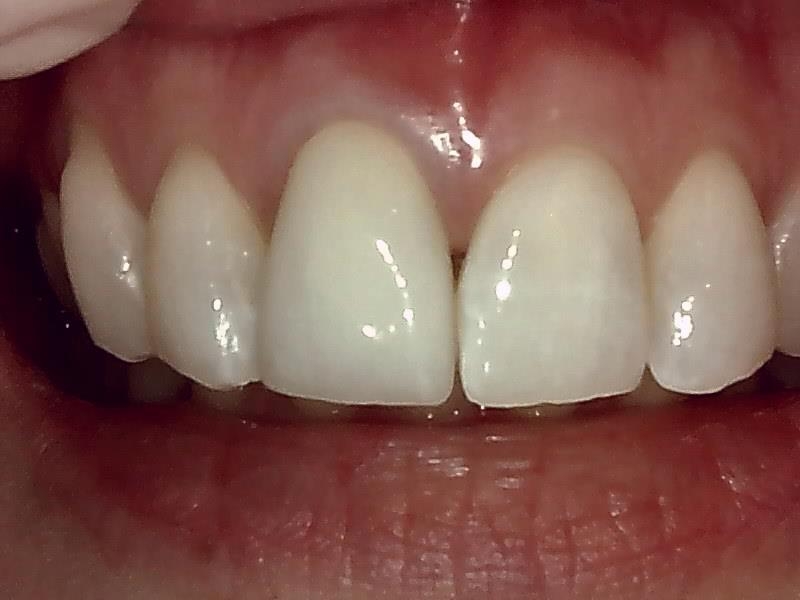

写真; ジルコニアセラミック冠装着

完成

治癒